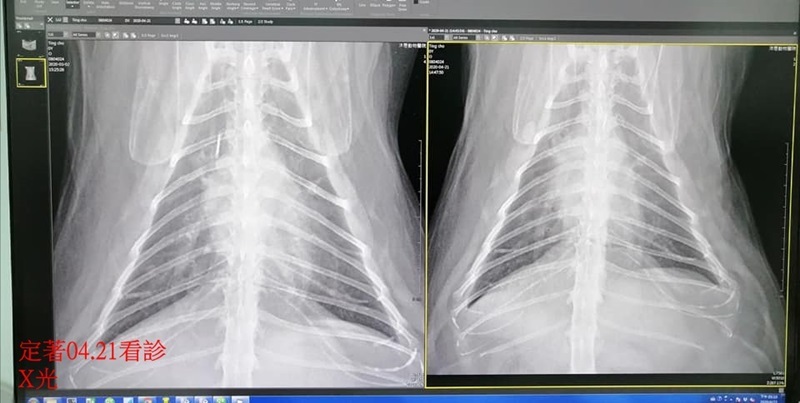

因定著出現頻繁咳嗽,於4月21日約診沐恩醫院檢查,血檢結果,肝指數升高很多,X光檢查沒有發現異常的變化,咳嗽與肝指數的升高,有可能是吃到清潔用品或過敏所致,先開口服藥治療,照護員也同時更換定著的食物,至5月5日回診追蹤,指數已恢復正常,且此期間也沒有再聽到定著咳嗽,目前仍須服用兩周藥,本筆醫助是定著再4月21日及5月5日至沐恩醫院的費用,包含血檢、用藥,請大家一起幫忙可愛的定著,謝謝大家。

定著近日出現咳嗽情況,X光檢查,與3月2日的X光片比較,並沒有太大變化。

血檢結果,crea1.9,bun27,AG比0.6,發炎指數5.0,紅白血球正常。

肝指數AST升高很多(今天86,去年12月31日是18,正常值0-48),這項指數升高,與食入清潔劑類用品或是食物改變有關,若排除吃到清潔劑用品的可能性及定著體重下降的情況,建議先更換食物。

袁醫師進行血液抹片檢查,與寄生蟲或過敏有關的嗜酸性球指數偏高,淋巴球較活躍,表示有慢性發炎的情況。

檢查結果,可能有初期的氣喘或支氣管炎,先針對咳嗽問題開化痰藥,另開備用的類固醇,二週後回診看咳嗽情況有無改善及追蹤肝指數。